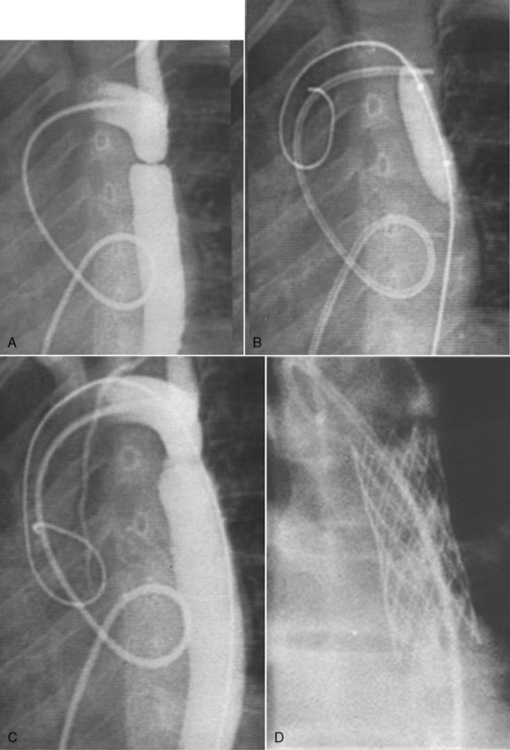

Vascular rings are created by abnormal branches of the aorta and systemic arteries that form a ring of vessels that encircle and potentially compress the trachea and esophagus. The most common vascular rings are created by a double aortic arch, a right aortic arch with left ligamentum arteriosus (the ligament formed after constriction of the ductus arteriosus or aberrant left subclavian artery), an anomalous innominate or left common carotid artery, or a pulmonary artery sling.930 These forms of vascular rings are illustrated and described in Table 8-39.459

During fetal life, six pairs of aortic arches are initially formed. These arches reform and involute, and they contribute to the formation of the aortic arch, the innominate and left subclavian arteries, and the right and left pulmonary arteries (see Evolve Fig. 8-1 in the Chapter 8 Supplement on the Evolve Website). If this process is disrupted, anomalies of the aortic arch and its major branches can result in the formation of a vascular ring. Anomalies of aortic arch formation have been found in patients with chromosome 22q-11 deletion.930

Management

The child with vascular ring and respiratory distress must be monitored closely because apnea and respiratory arrest may develop. Surgical intervention is planned during infancy to remove the tracheal compression so the trachea can grow.

Surgical intervention is accomplished through a thoracotomy incision. If a double aortic arch is present, the smaller (remnant or diminutive) arch is tied and divided, and the ligamentum arteriosus also is divided. If an anomalous innominate artery is contributing to tracheal compression, it often is pulled away from the trachea and suspended by sutures from the posterior portion of the sternum. If a pulmonary artery sling is present the anomalous pulmonary vessel usually is ligated, and an anastomosis is performed anterior to the trachea between the anomalous pulmonary vessel and the left pulmonary artery.